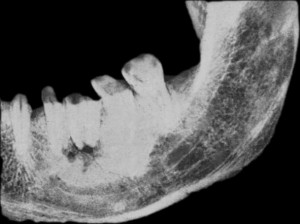

Визуальное и рентгенографического исследование нижней челюсти древнеегипетской мумии, проведённое в 1917 г., выявило два симметричных и параллельных трепанационных канала, начинающихся в кортикальной пластинке, чуть выше ментального отверстия нижней челюсти, и заканчивающихся у верхушки медиального корня первого моляра. Данный канал был просверлен первобытным бором для создания оттока из гнойного очага в области верхушки корня.

- Трепанация нижней челюсти

- Рентгенография периодонтита